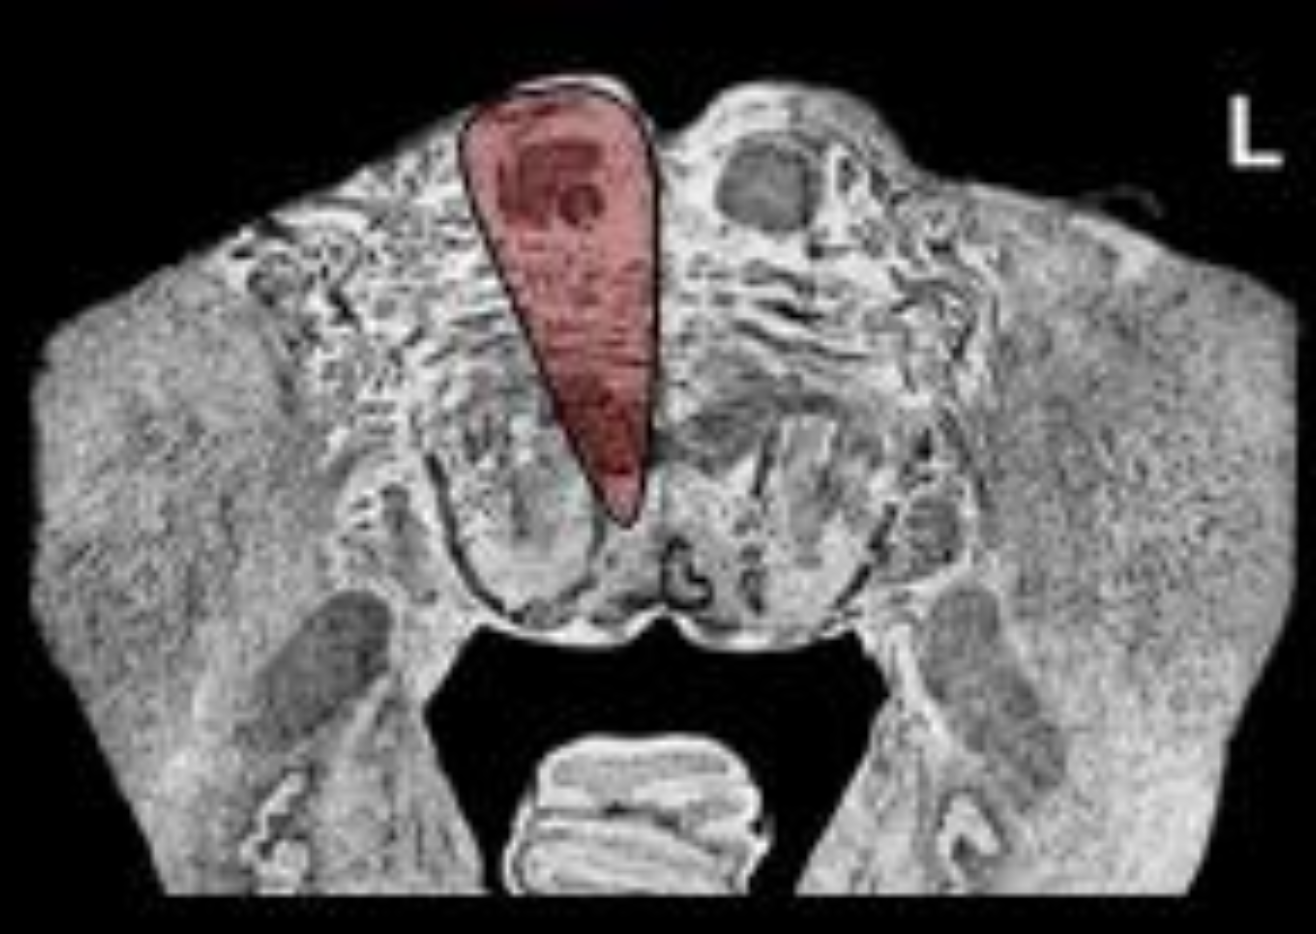

What is the name/location/results of the condition caused by a lesion in the shaded area?

Medulla at mid olive

Alternating Hypoglossal Hemiplegia and destruction of the ipsilateral Medial Lemniscus